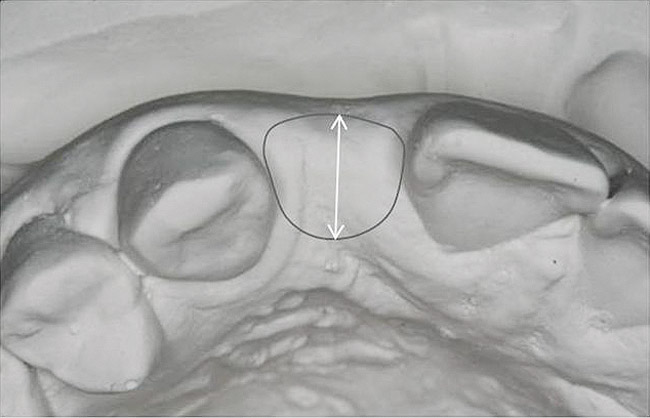

Figure 7  These images summarize the various dimensional assessments that underscore the Rules of Six guidelines, which enable simple planning for uncomplicated single-tooth dental implant therapy: Finding mesiodistal or inter-radicular (Fig 7), buccolingual (Fig 8), and inter-occlusal (Fig 9) distances of 6 mm can assure uncomplicated implant placement and restoration.

Figure 7

Figure 8  These images summarize the various dimensional assessments that underscore the Rules of Six guidelines, which enable simple planning for uncomplicated single-tooth dental implant therapy: Finding mesiodistal or inter-radicular (Fig 7), buccolingual (Fig 8), and inter-occlusal (Fig 9) distances of 6 mm can assure uncomplicated implant placement and restoration.

Figure 8